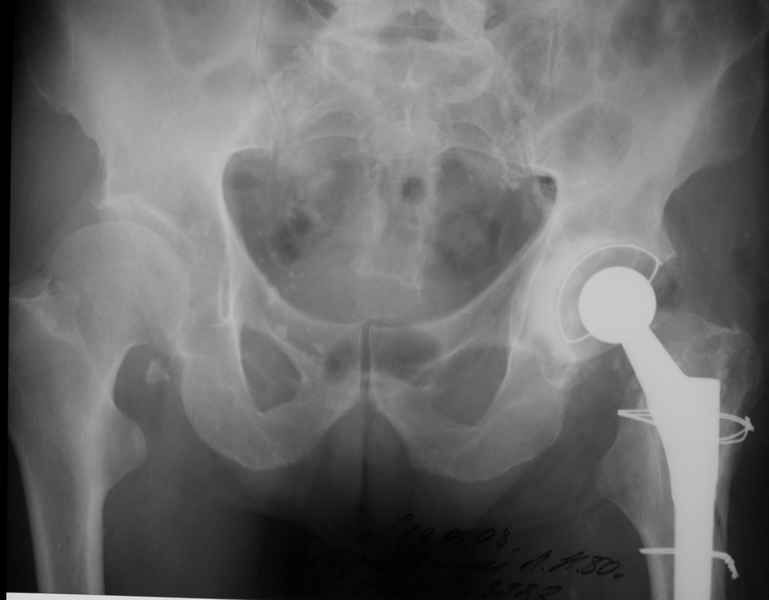

Re: Перипротезный перелом

Уважаемые коллеги, продолжая дискуссию, начатую на "Вреденовских чтениях", хочу сказать, что принципиально сущестует два возможных варианта лечения.

1.Остеосинтез на ножке. Мне кажется, что применительно к этому случаю малоперспективный вариант. Синтез хорош, когда можно его выполнить в малоинвазивном исполнении и достигнуть стабильности. Действительно, если ножка б/цементной фиксации после этого не будет иметь фиксации, то ревизия не будет иметь проблем. В представленном случае стабильность синтеза сомнительная, а проведение доп.иммобилизации приведет к контрактуре суставов.

2. Применение ножки дистальной фиксации, мы отдаем предпочтение ножке Вагнера с фиксацией проксимального отдела на ножке. Более травматичное вмешательство, но при стабильной фиксации ножки реабилитация идет в обычном режиме.

Хочется показать два подобных случая, П-ка З. 72 лет и п-т Г. 80 лет. Сразу принимаю замечание, что это были ножки цементной фиксации, просто под руками не было бесцементника.